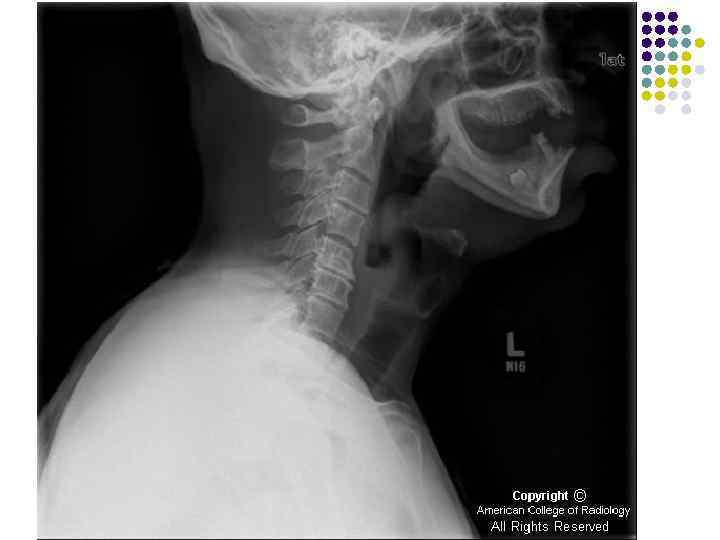

l l l На рентгенограмме шейного отдела позвоночного столба в боковой проекции определяется: выраженные распространенные дистрофические изменения в виде остеохондроза и артроза дугоотростчатых суставов: неравномерное сужение межпозвонковых пространств, субхондральный остеосклероз, костные разрастания по краям тел позвонков, сужение рентгеновских суставных щелей дугоотостчатых суставов с субхондральным остеосклерозом и небольшими костными разрастаниями по краям суставных поверхностей. Наиболее ярко эти изменения выражены в сегментах С 5 -6 -7 Признаки ограниченного смещения тел позвонков в виде симптома «распорки» и кифотической установки. Заключение: Остеохондроз шейного отдела позвоночного столба. Артроз дугоотростчатых суставов. Деформация шейного отдела позвоночника с нарушением статики.

1.

l l l На рентгенограмме шейного отдела позвоночного столба в боковой проекции определяется: выраженные дистрофические изменения за счет остеохондроза - значительное, неравномерное сужение межпозвонковых пространств с нарушением их правильной клиновидной формы, выраженный субхондральный остеосклероз, значительные костные разрастания по передним краям тел позвонков. Наиболее ярко эти изменения представлены в сегментах С-5, 6, 7. Помимо этого, в этих же сегментах фиксируются дистрофические изменения дугоотростчатых суставов – сужение рентгеновских суставных щелей, субхондральный остеосклероз и костные разрастания по краям суставных поверхностей. Выпрямление физиологического лордоза. Признаки системного нарушения статики тел позвонков в виде симптомов кифотической установки. Деструктивных изменений нет Заключение: Комплекс дистрофических изменений шейного отдела позвоночного столба в виде остеохондроза и артроза дугоотростчатых суставов с преимущественными проявлениями в нижних сегментах отдела. Нарушение статики тел позвонков